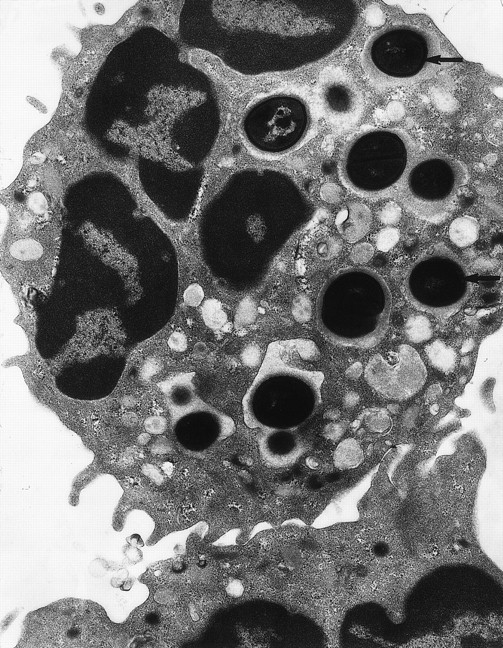

The neutrophil makes tight contact with its target and the plasma membrane flows around the surface until the bacterium is completely enclosed.88 This minimizes the amount of extracellular fluid entering the phagosome with the bacterium, and means that the phagosome is initially a very small space (Fig 3). The exclusion of external medium sets up a new environment that will have an important influence on the biochemistry of oxidant production and bacterial killing. The major contributors to the chemical composition of the phagosome are the contents of the cytoplasmic granules that empty into it. Granule contents are released within seconds of ingestion and constitute a significant proportion of the phagosomal volume.3,89 There are at least four different classes of granules,90 and sequential release of the different types90 91 may provide a succession of different phagosomal environments.

Transmission electron micrograph of S aureusinside the phagosome of a human neutrophil. Arrows pointed to examples of S aureus within phagosomes (original magnification × 15,000). (Courtesy of W.A. Day, Department of Pathology, Christchurch School of Medicine.)